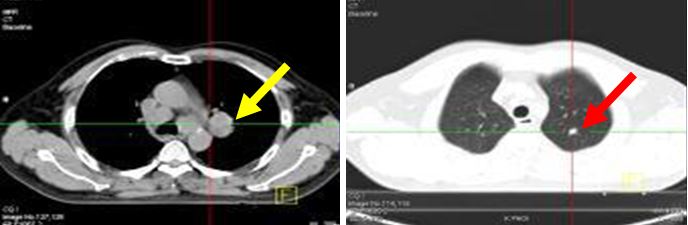

CHỤP CT NGỰC

Khối u rốn phổi trái kích thước 3x3,5cm. Nốt mờ thùy trên phổi trái kích thước 1,2cm.

Hình ảnh khối u rốn u rốn phổi trái KT 4x4,5cm tăng hấp thu FDG mạnh, SUV=12,3.

Di căn hạch trung thất và hạch rốn phổi hai bên kích thước lớn nhất 2,5x3,6cm, SUV=6,8.

Di căn hạch trung thất tăng hấp thu FDG, nốt mờ thùy trên phổi trái tăng hấp thu FDG